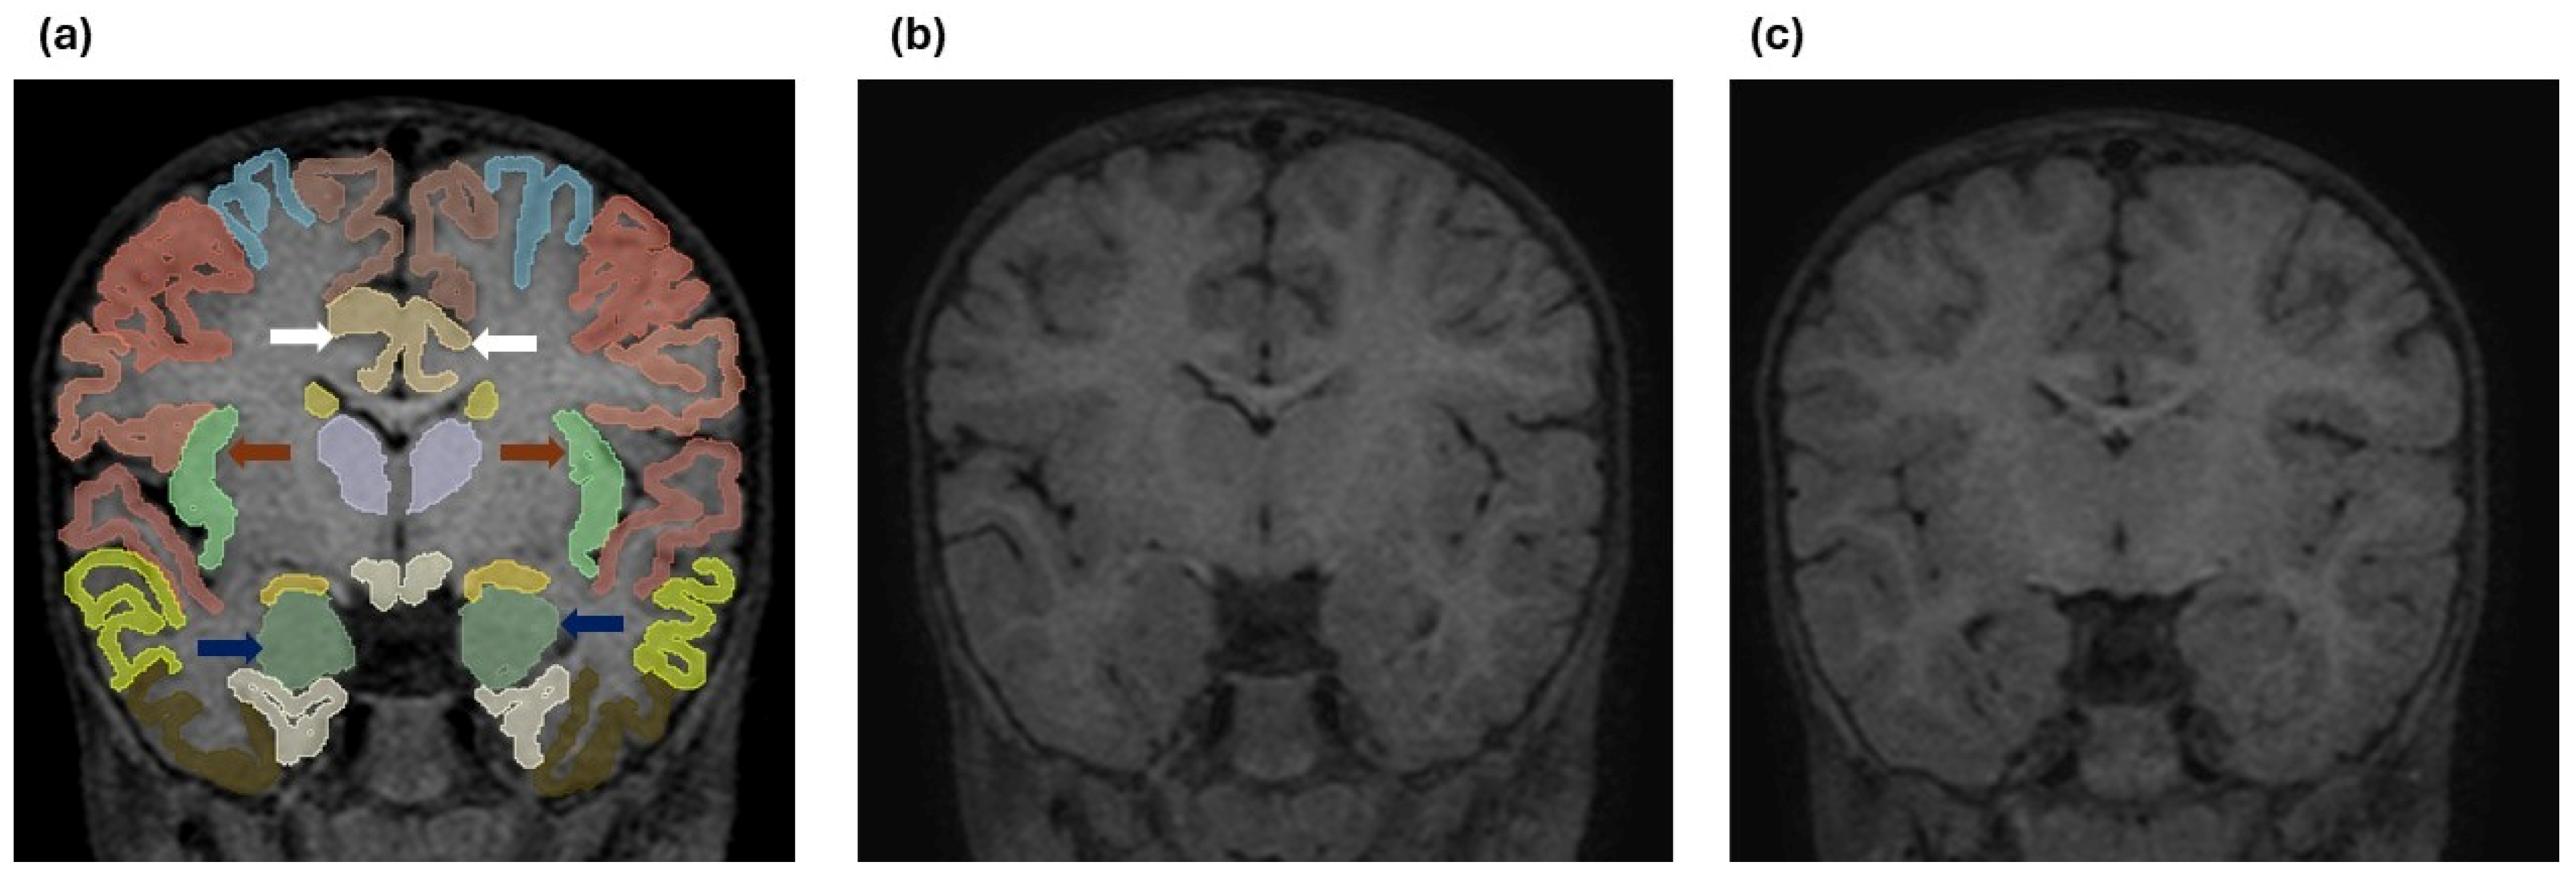

To illustrate the automated brain parcellation process, Figure 2 presents an example of cortical and subcortical segmentation performed using the Vol2Brain pipeline based on high-resolution 3D T1-weighted MRI data.

Figure 2. (a) Coronal T1-weighted MR image demonstrating automated cortical and subcortical parcellation performed using the Vol2Brain pipeline based on high-resolution 3D T1-weighted MRI data. Color-coded regions represent anatomically defined cortical and subcortical structures. Dark blue arrows indicate the bilateral amygdala, brown arrows indicate the bilateral anterior insular cortex, and white arrows indicate the bilateral caudal anterior cingulate gyrus. (b) Coronal 3D T1-weighted MR image obtained at a comparable anatomical level from a 1-year-old patient with breath-holding spells. (c) Coronal 3D T1-weighted MR image obtained at a similar level from a 1-year-old subject in the control group.